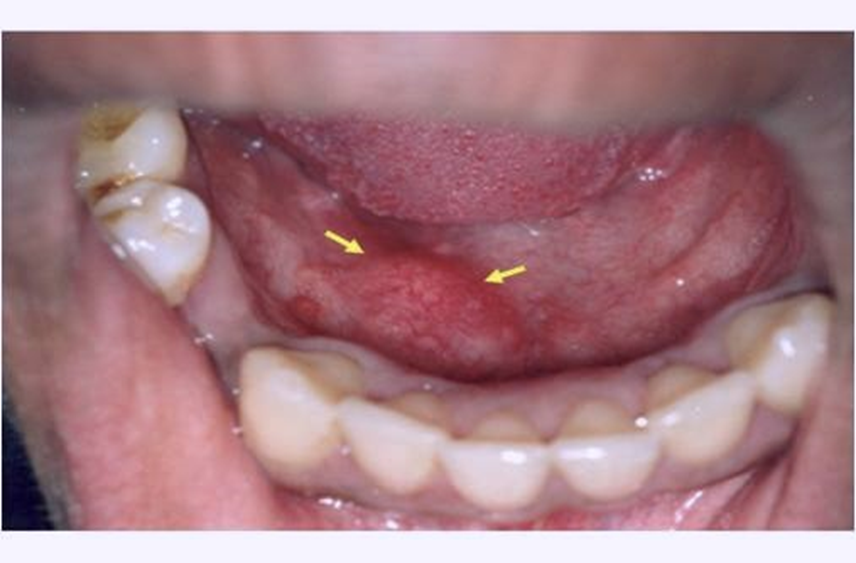

3. Kanker Mulut

Kanker mulut merupakan penyakit berbahaya pada mulut dan gigi. Jenis kanker ini dapat mempengaruhi jaringan apapun di dalam mulut, mulai dari dinding mulut, bibir, lidah, gusi atau langit-langit mulut. Kanker mulut juga dapat terjadi pada jaringan tenggorokan (faring) dan kelenjar ludah.

Pengguna tembakau, seperti perokok atau pengunyah tembakau, berada pada peningkatan risiko terkena kanker mulut. Gejala kanker mulut yang paling khas adalah munculnya sariawan yang tidak kunjung hilang, muncul bintik-bintik putih atau merah dan rasa sakit di mulut.